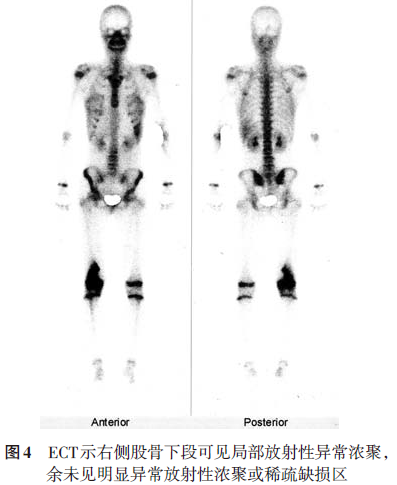

显示心、肺、膈均未见明显异常。正、侧位X线片(2008.6.14)示右股骨远端可见半圆形骨破坏区,骨小梁及内侧骨皮质破坏,边界模糊,内侧缘三角形骨膜反应,局部软组织肿块,提示右股骨恶性肿瘤,膝关节未见明显异常(图1)。CT(2008.6.17)示右侧股骨下段干骺端骨质密度不均匀,内侧骨皮质破坏,骨膜增厚外突(图2)。MRI(2008.6.16)示右侧股骨远端干骺端内侧见骨质破坏,周围见软组织肿块影;T1加权像呈等低信号,T2加权像呈稍高信号,病灶周围见骨膜反应并可见Codman三角,注射造影剂后见轻度对比增强(图3)。ECT(2008.6.17)静脉注射骨显像剂3h后行全身前后位骨显像,骨显像尚清晰,右侧股骨下段可见局部放射性异常浓聚,余未见明显异常放射性浓聚或稀疏缺损区(图4)。